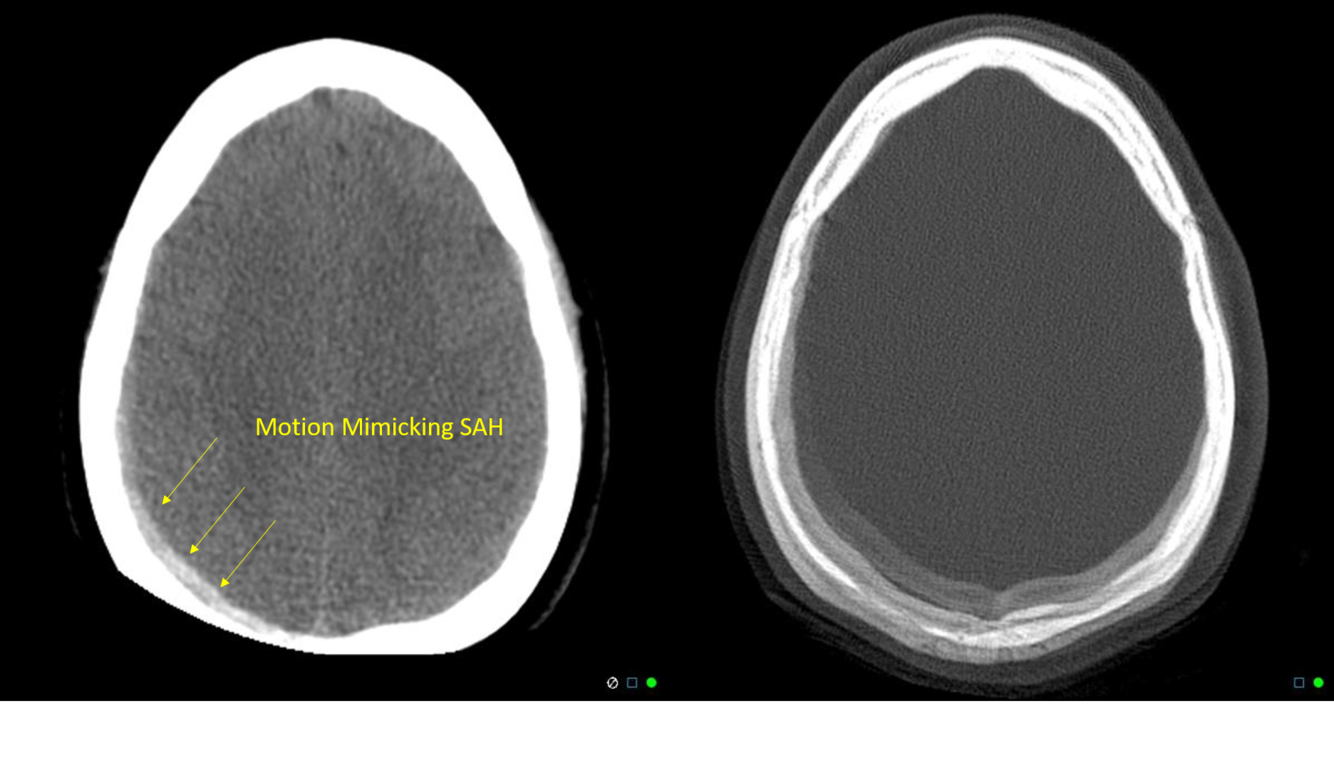

The streak artifact in this case is caused by the arms of the patient being in above the head position and outside the scan FOV.

When anatomy or anything else somewhat dense (IV bags, monitoring equipment) is outside the scan FOV, it will only be seen by the scanner on some projections (incomplete projection artifact) and cause errors in the reconstruction, resulting in streaking. The geometry of the streak artifact converges outside the FOV and not at the calvarium and thus cannot be beam hardening artifact, which would be more pronounced at lower kVp settings.